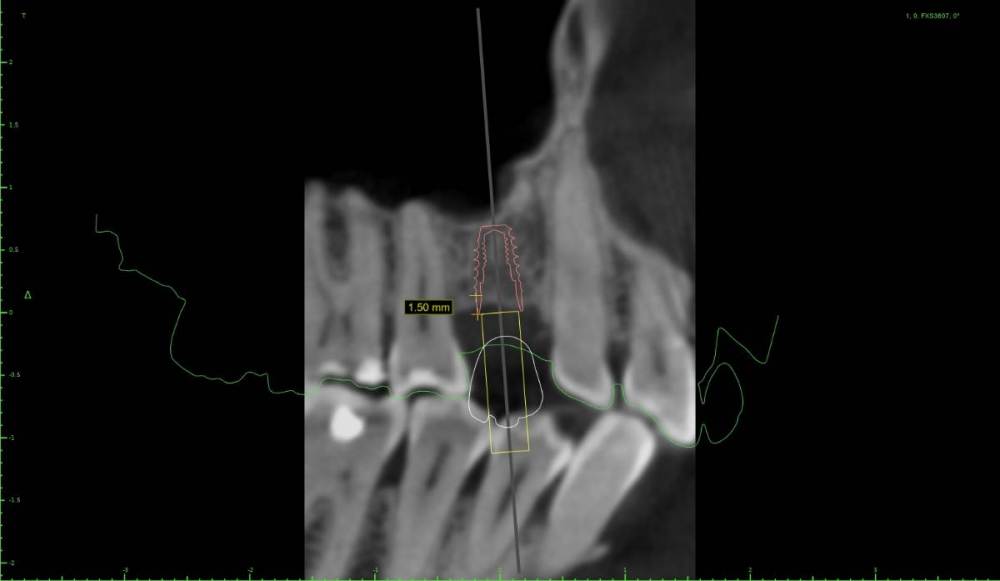

Женька Опубликовано 22 мая, 2021 Поделиться Опубликовано 22 мая, 2021 Дабы не захламлять тему про "мильён вопросов" я всё же создал свою. Итак, я получил оттиск верхней челюсти, отлил модель и перевёл в stl. Мои остеотомы застряли где-то в Пуяне и постучать нечем. Но в теме с мильёном вопросов пришли к выводу, что и зсл не нужен, только нкр. Что под рукой: даск с его фрезами для зсл, мембрана еволюшн, микс апатоса и только нитки, чтобы всё это зафиксировать. Также есть вариация имплантата суперлайн 2 (1.5мм полированной шейки и 5.5 шероховатой) или же полностью шероховатый суперлайн 1 с полированной фаской (3.6*7мм), но макродизайн менее агрессивный. Также будет сделан шаблон под пилотное сверление. Вот такие варианты получились. Вопрос, можно ли будет сделать маленькую нкр с имплантатом имеющим 1.5мм полированную шейку (как я понимаю - нет)? Ссылка на комментарий

Карен Аванесов Опубликовано 31 мая, 2021 Поделиться Опубликовано 31 мая, 2021 Делайте ту операцию в качестве которой и дальнейшем прогнозе Вы уверены. Лично я, в такой ситуации, устанавливаю имплантат 7мм. 1 1 Ссылка на комментарий

Pavel-Pskov Опубликовано 31 мая, 2021 Поделиться Опубликовано 31 мая, 2021 + за короткий. Ссылка на комментарий

Bier Опубликовано 3 июня, 2021 Поделиться Опубликовано 3 июня, 2021 я бы тут пластику не делал, только мягкие ткани. Ну имплантат в пазуху бы ткнул немного 1 Ссылка на комментарий